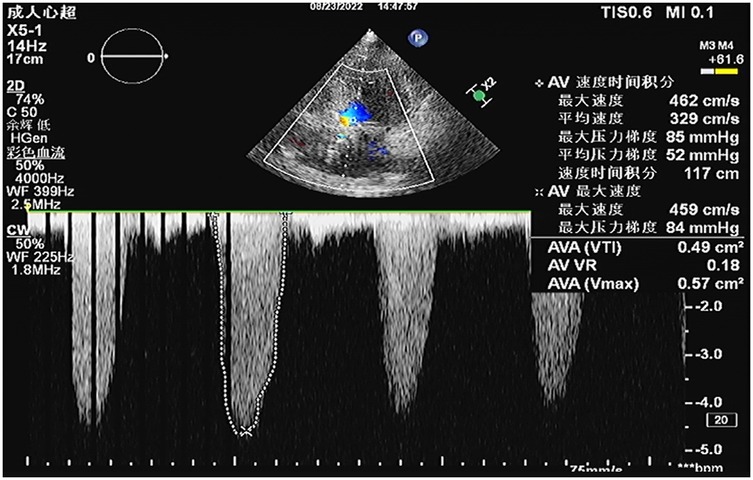

A 64-year-old female patient presented with persistent shortness of breath for two days, which was aggravated by mild exertion, and an inability to lie flat at night. Her medical history included hypertension and a cerebrovascular accident (stroke) for over 10 years. Upon admission, the patient was alert, and physical examination revealed a systolic ejection murmur at the aortic valve area, a systolic blowing murmur at the mitral valve area, and moist rales in both lungs. A 12-lead electrocardiogram indicated sinus rhythm, with a Q wave in lead III, T-wave inversion in leads I and aVL, and ST-segment elevation of approximately 0.1 mV in leads V1–V4. Leads V5 and V6 exhibited flat T-waves. Laboratory tests revealed troponin I level of 2.400 ng/ml (reference: 0.010–0.023 ng/ml) and N-terminal pro-B-type natriuretic peptide levels of 2030.00 ng/L (reference: 300.00–900.00 ng/L). Transthoracic echocardiography (TTE) demonstrated severe AS with moderate aortic regurgitation, a peak aortic valve flow velocity of 4.6 m/s, and a mean transvalvular pressure gradient of 52 mmHg (Figure 1). Severe mitral regurgitation was noted, with a regurgitant area of 10 cm2. There was generalized left ventricular hypokinesis, and the left ventricular ejection fraction (LVEF) was 36.6%.

Figure 1

Preoperative transthoracic echocardiography (TTE) revealed severe aortic valve stenosis with a peak transvalvular velocity of 4.6 m/s, peak pressure gradient (PG) of 85 mmHg, mean pressure gradient (mPG) of 52 mmHg, aortic valve area (AVA) by velocity-time integral (VTI) of 0.49 cm2, and aortic regurgitant area of 4.6 cm2.